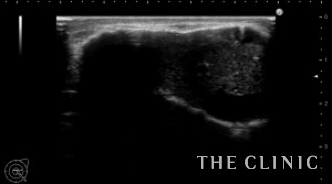

エコー所見です。

右 被膜が石灰化もしています。